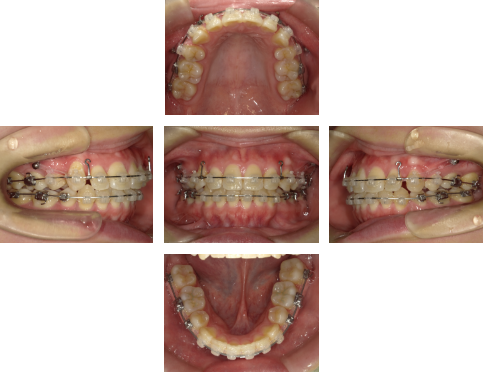

【治療中】

歯列が整ったあと、口蓋側壁にアンカースクリュー(水色の◯の箇所)を併用し、前歯を後方へ移動させました。

※関連記事:アンカースクリュー特集>>